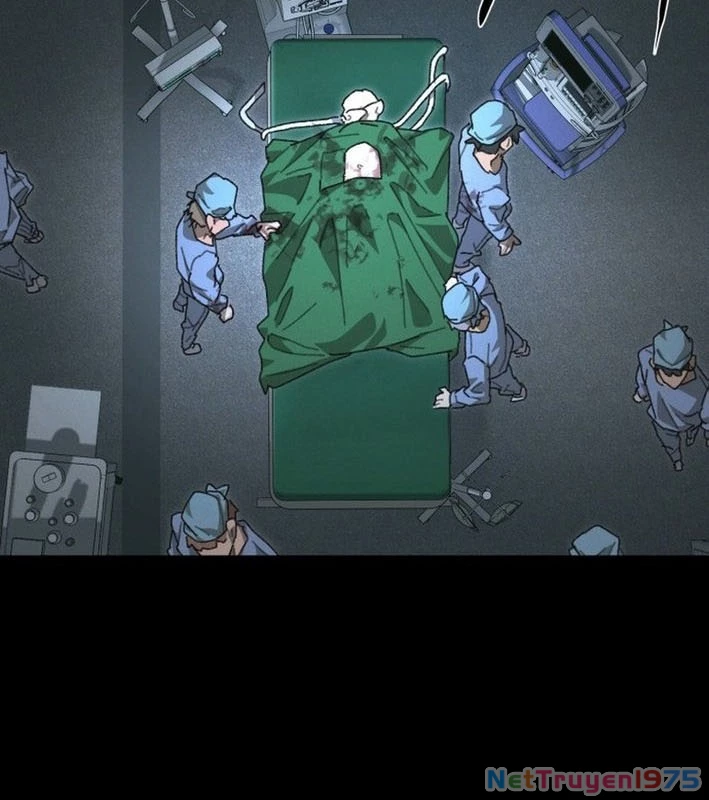

Kẻ Chôn Cất Quái Vật - Chapter 1